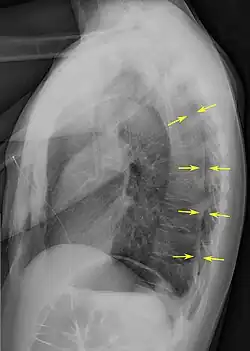

Chest X-ray

A plain chest radiograph, ideally with the X-ray beams being projected from the back (posteroanterior, or "PA"), and during maximal inspiration (holding one's breath), is the most appropriate first investigation.[35] It is not believed that routinely taking images during expiration would confer any benefit.[36] Still, they may be useful in the detection of a pneumothorax when clinical suspicion is high but yet an inspiratory radiograph appears normal.[37] Also, if the PA X-ray does not show a pneumothorax but there is a strong suspicion of one, lateral X-rays (with beams projecting from the side) may be performed, but this is not routine practice.[18][22]

It is not unusual for the mediastinum (the structure between the lungs that contains the heart, great blood vessels, and large airways) to be shifted away from the affected lung due to the pressure differences. This is not equivalent to a tension pneumothorax, which is determined mainly by the constellation of symptoms, hypoxia, and shock.[16]

The size of the pneumothorax (i.e. the volume of air in the pleural space) can be determined with a reasonable degree of accuracy by measuring the distance between the chest wall and the lung. This is relevant to treatment, as smaller pneumothoraces may be managed differently. An air rim of 2 cm means that the pneumothorax occupies about 50% of the hemithorax.[18] British professional guidelines have traditionally stated that the measurement should be performed at the level of the hilum (where blood vessels and airways enter the lung) with 2 cm as the cutoff,[18] while American guidelines state that the measurement should be done at the apex (top) of the lung with 3 cm differentiating between a "small" and a "large" pneumothorax.[38] The latter method may overestimate the size of a pneumothorax if it is located mainly at the apex, which is a common occurrence.[18] The various methods correlate poorly but are the best easily available ways of estimating pneumothorax size.[18][22] CT scanning (see below) can provide a more accurate determination of the size of the pneumothorax, but its routine use in this setting is not recommended.[38]

Not all pneumothoraces are uniform; some only form a pocket of air in a particular place in the chest.[18] Small amounts of fluid may be noted on the chest X-ray (hydropneumothorax); this may be blood (hemopneumothorax).[16] In some cases, the only significant abnormality may be the "deep sulcus sign", in which the normally small space between the chest wall and the diaphragm appears enlarged due to the abnormal presence of fluid.[19]